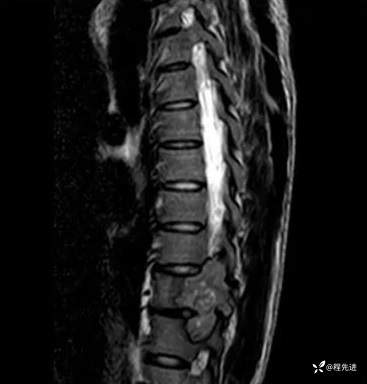

MR:

T2: